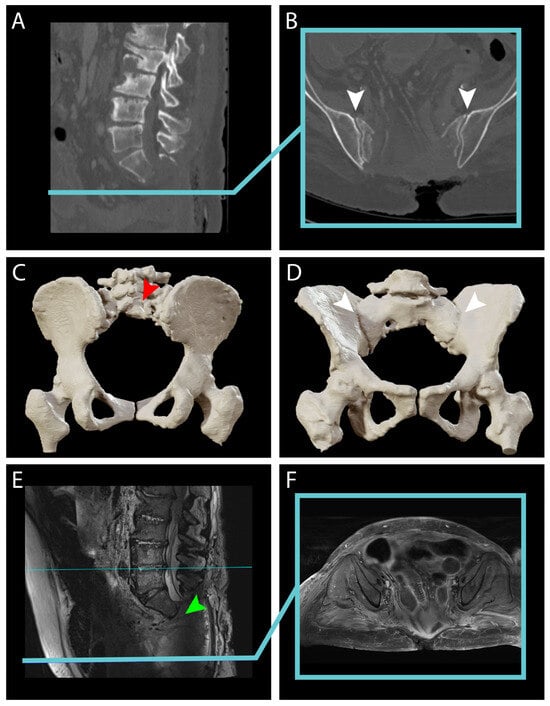

4. Results: Illustrative Case

4.1. Clinical Elements

4.2. Preoperative Planning